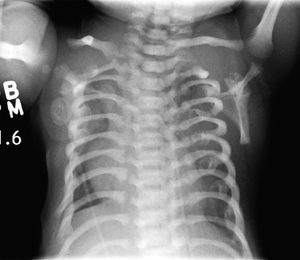

CXR of a newborn with asphyxiating thoracic dysplasia. Note the short ribs. | |